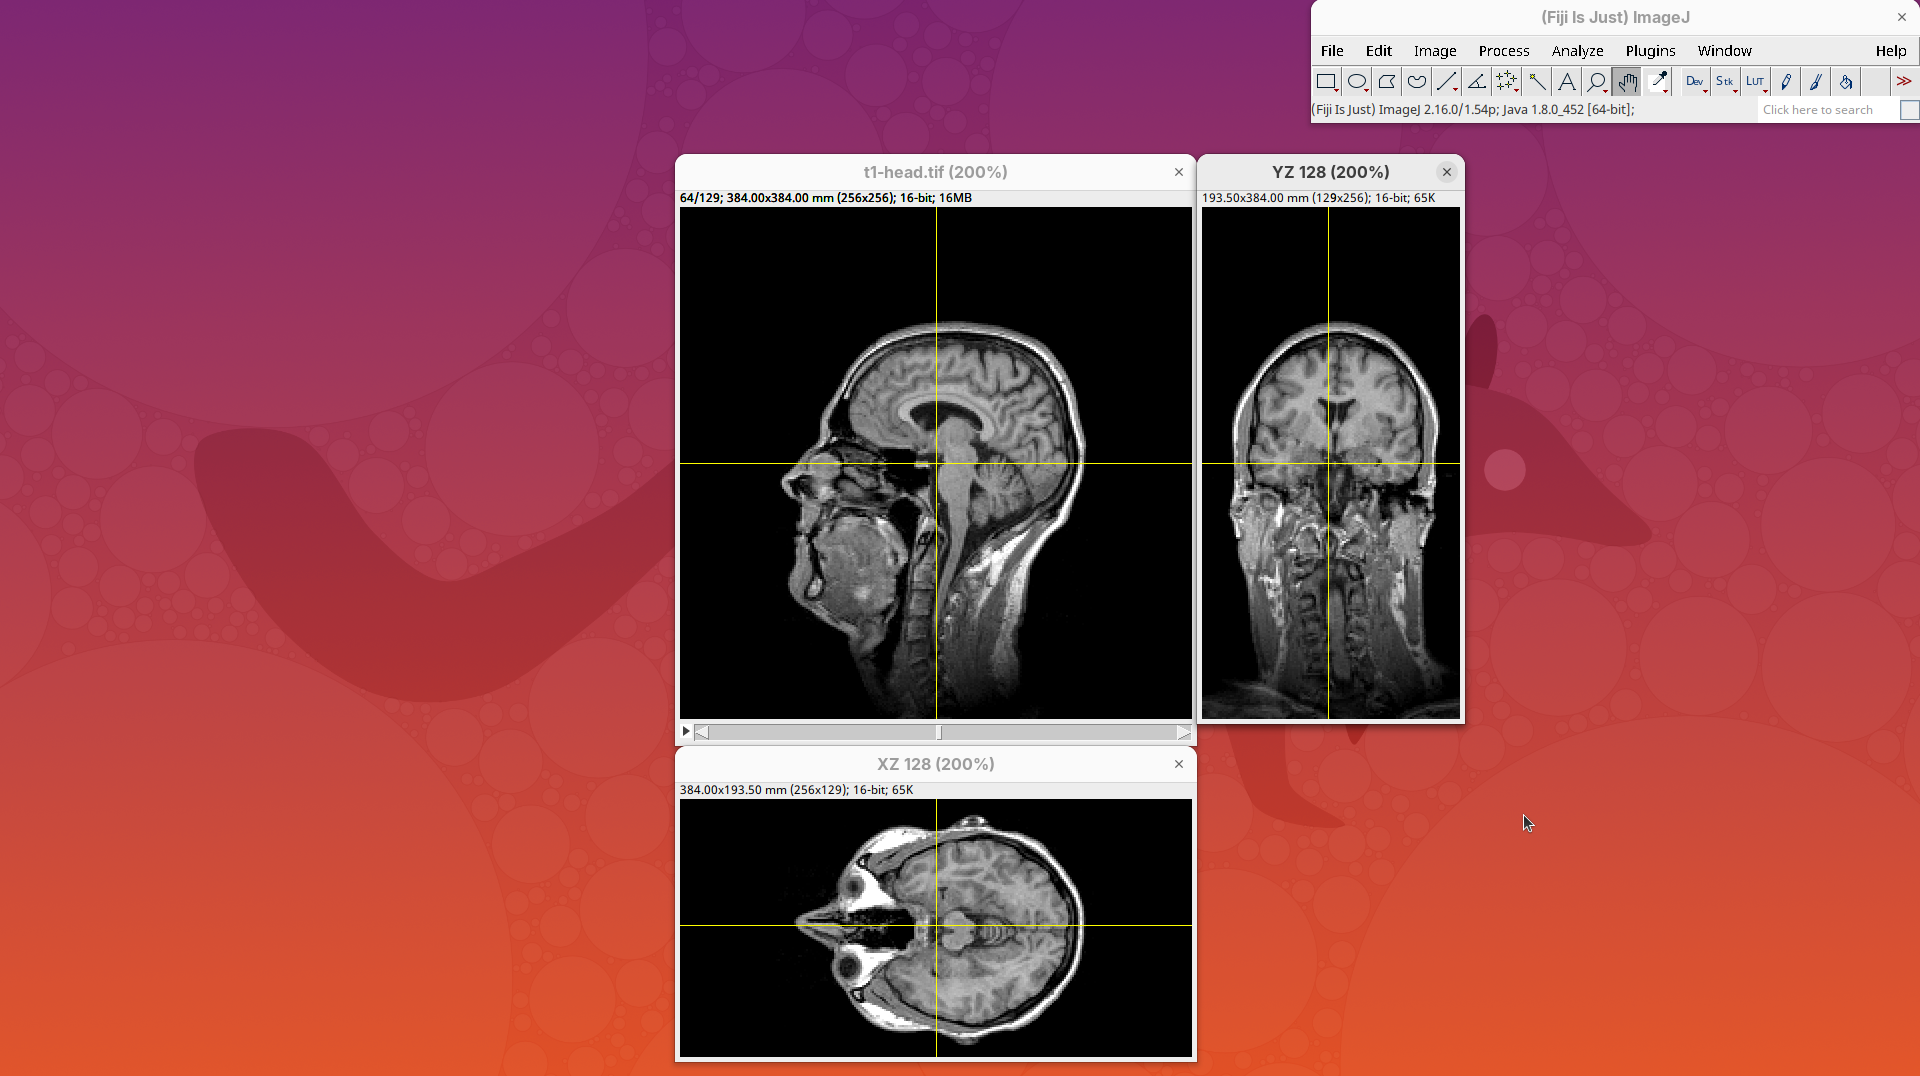

Orthogonal Views

Orthogonal Views is a tool that shows the optical sections through the orthogonal planes of XY: XZ and YZ. It is an easy and quick way to get a sense of the tridimensionality of your dataset. Whenever I’m opening a dataset for the first time I use Orthogonal Views. To activate it:

- Click on

Image>Stacks>Orthogonal Views(or pressCtrl+Shift+H). - The XZ and YZ panels will open next to your XY stack.

- The yellow lines are synchronized between the panels.

- Click around the different parts of the head to inspect the same position under different angles.

Orthogonal Views is a great way to start understanding your 3D data.